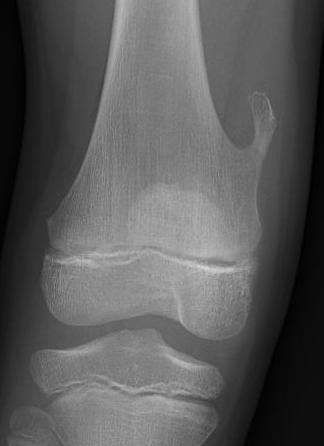

X-ray

Cortical and marrow continuity

Types

1. Pedunculated - has a stalk, points away from joint

2. Sessile - attaches to bone with a broad base

Pedunculated

Protuberant bony lesion arising adjacent to physis

- directed away from joint

- cortical bone and marrow space continuous

Sessile